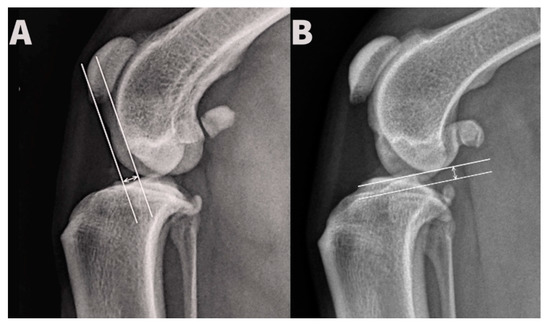

Displacement of the femoral hemicondyles was established by three blinded observers for each radiograph. Cranio-caudal displacement was determined by drawing two lines parallel with the long tibial axis, aligned with most caudal aspects of the medial and lateral femoral hemicondyles, respectively, and measurement of the distance between them. Proximo-distal displacement was determined by drawing two lines perpendicular to the long tibial axis, aligned with the most distal aspects of the medial and lateral femoral hemicondyles, respectively, and measurement of the distance between them (Figure 2). Identification of the fossa of insertion of the tendon of the extensor digitorum longus and the more typically rounded shape of the lateral femoral hemicondyle allowed radiographic distinction between medial and lateral hemicondyles. All distances were measured in millimeters.

Figure 2. Measurement of the cranio-caudal (A) and proximo-distal (B) distance between the medial and lateral condyle.